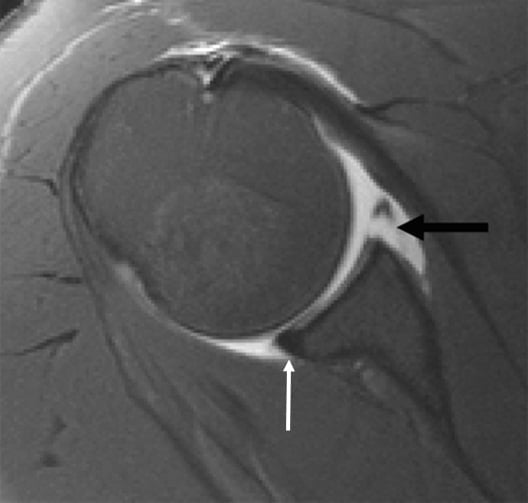

Η διάγνωση περιλαμβάνει κατά κύριο λόγο την λήψη ιστορικού και την κλινική εξέταση. Ο κ. Παναγόπουλος θα λάβει αναλυτικό ιστορικό και θα σας εξετάσει. Μία ακτινογραφία του ώμου θα βοηθήσει να αποκλειστούν άλλα αίτια πόνου, όπως οστεοαρθρίτιδα του ώμου ή ασβεστοποιός τενοντίτιδα. Ο κ. Παναγόπουλος θα σας υποβάλλει σε υπερηχογράφημα ώμου, για να επιβεβαιώσει την παρουσία ρήξεων στο στροφικό πέταλο. Ο υπέρηχος ελέγχει το πάχος του τένοντα, αλλά βοηθάει και στη δυναμική αξιολόγηση της πρόσκρουσης. Σε ορισμένες περιπτώσεις, ο ιατρός θα σας παραπέμψει για μαγνητική τομογραφία για την αξιολόγηση του μεγέθους της ρήξης ή τυχόν ατροφίας των μυών.